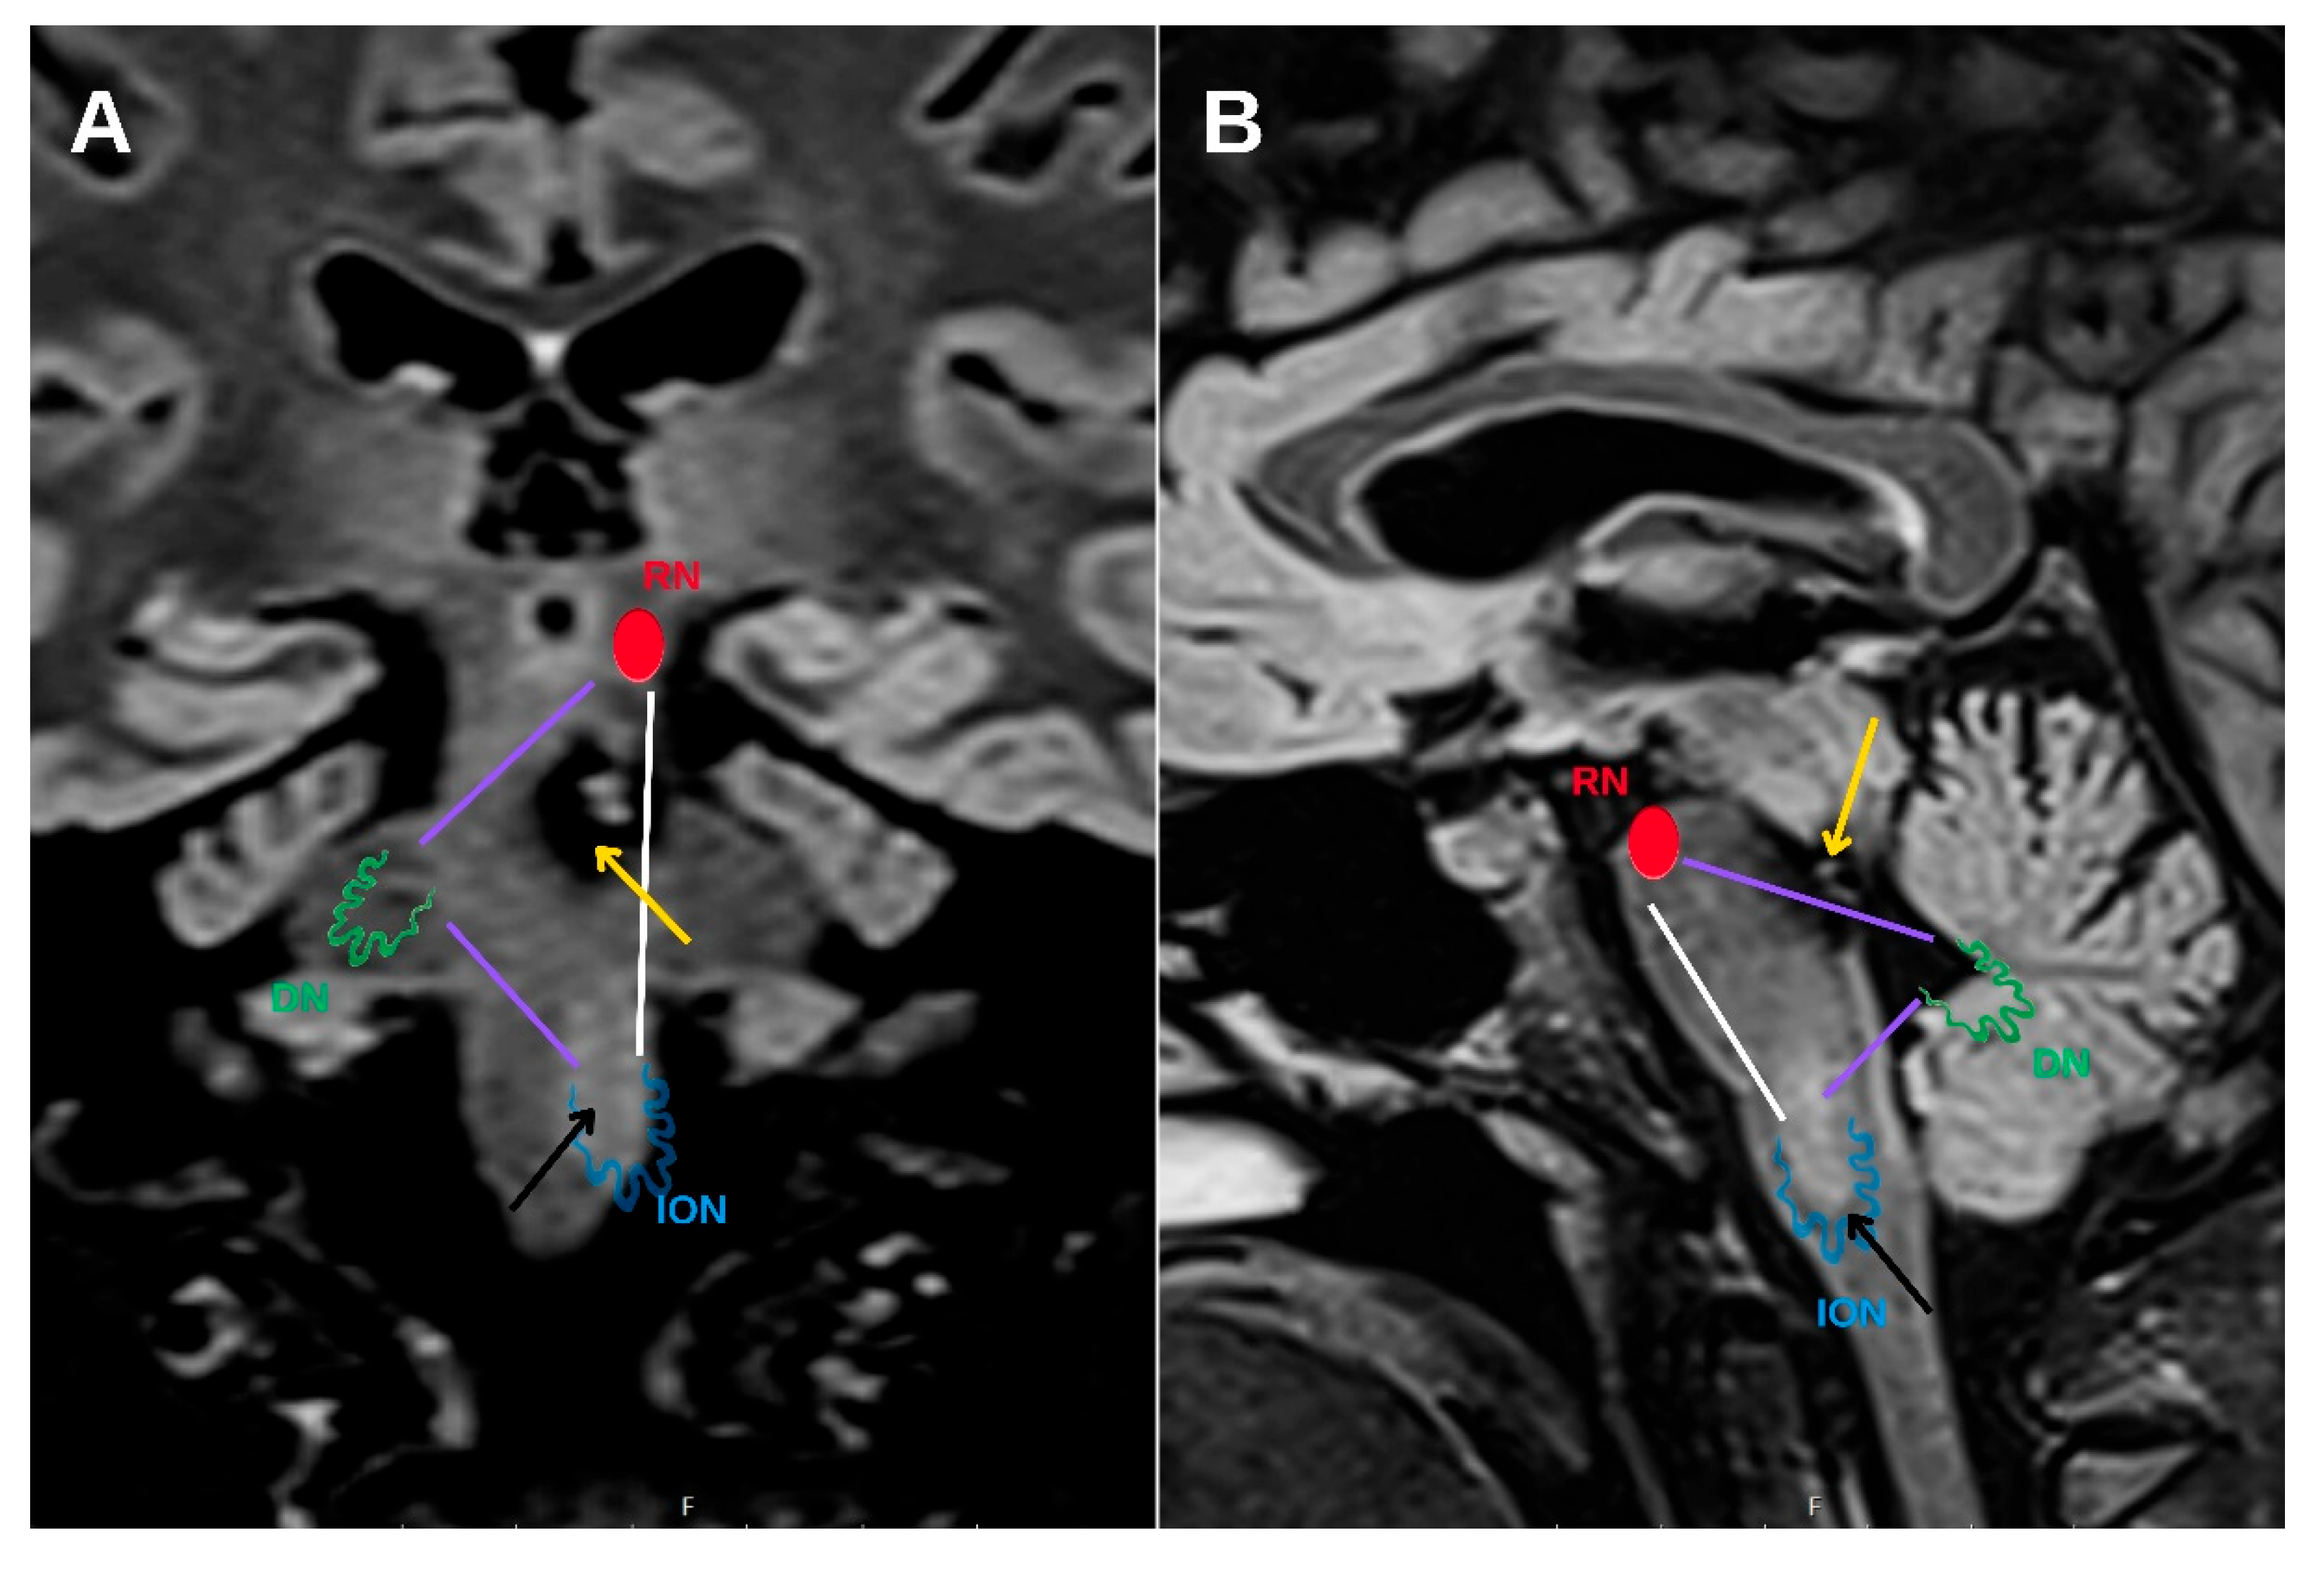

Hypertrophic olivary degeneration (HOD) is an uncommon form of trans-synaptic degeneration that affects the dentato-rubro-olivary pathway, also known as the Guillain–Mollaret triangle (

Figure 1). This neural circuit includes the red nucleus in the midbrain, the ipsilateral inferior olivary nucleus (ION) in the medulla oblongata, and the contralateral dentate nucleus of the cerebellum, interconnected via the central tegmental tract and superior cerebellar peduncle [

HOD represents a distinct form of trans-synaptic degeneration characterized by hypertrophy rather than atrophy of the ION, most frequently resulting from disruption of the dentato-rubro-olivary pathway, commonly referred to as the Guillain–Mollaret triangle [

1]. This anatomical circuit comprises the contralateral dentate nucleus, the ipsilateral red nucleus, and the ipsilateral ION, interconnected via the superior cerebellar peduncle and the central tegmental tract. Lesions affecting any component of this circuit—particularly the central tegmental tract—may lead to secondary degeneration of the ION (

Figure 6).